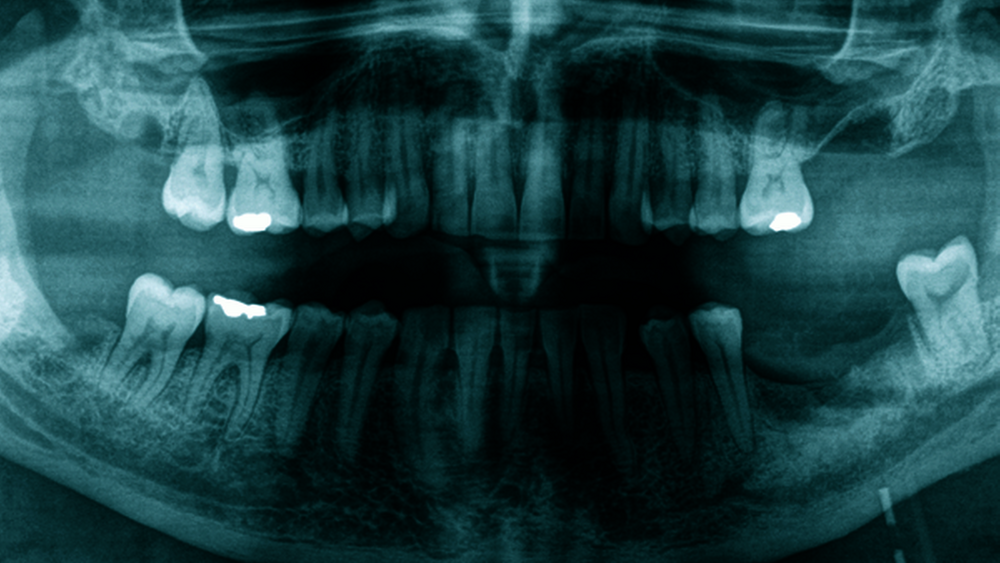

Es wurden eine Blutentnahme, die laborchemisch nur diskret erhöhte Infektparameter ergab, eine Panoramaschichtaufnahme und eine Sonografie der Halsweichteile durchgeführt. Hierbei konnte eine 5 cm x 3,5 cm messende submandibuläre Raumforderung mit muskelisodensem Randsaum und echoleerem Zentrum dargestellt werden. Aufgrund der Verdachtsdiagnose eines perimandibulären Abszesses – ausgehend von einem parodontal stark geschädigten Zahn 37 – wurden eine Abzesseröffnung von extraoral und eine Extraktion der oben genannten Zähne in Intubationsnarkose durchgeführt. Hierbei konnte massiv putrides, blutig tingiertes Sekret entlastet werden. Nach mikrobiologischer Abstrichnahme und ausgiebiger Wundspülung wurde lingual und pterygomandibulär je ein Drainageröhrchen nahtfixiert eingebracht (Abbildung 1) und der Patient nach der Aufwachphase zur täglichen Spülung und i.v.-Antibiose (Ampicillin/Sulbactam 3 g i.v. dreimal pro Tag) auf die Normalstation verlegt.

Bei der Aufnahmeuntersuchung zeigte sich extraoral eine ausgeprägte indurierte Schwellung, die den linken Unterkiefer umgab, der Unterkieferrand war im Bereich des Corpus mandibulae nicht mehr durchtastbar. Der Patient klagte über mäßige Schluckbeschwerden, die Mundöffnung war leicht eingeschränkt, Atemnot bestand nicht. Intraoral zeigte sich ein konservierend versorgtes Gebiss mit parodontal stark geschädigten Zähnen 18, 28, 37 und 48. Diese Zähne wiesen eine zweit- bis drittgradige Lockerung auf. Zusätzlich war der Zahn 37 stark nach mesial gekippt. Die Zähne des dritten Quadranten waren sensibel und wiesen keine Perkussionsempfindlichkeit auf. Weiterhin stellten sich in dieser Region ein verstrichenes Vestibulum und ein linksseitig leicht angehobener Mundboden dar. Außer der generalisierten gingival-parodontalen Entzündung waren keine weiteren Schleimhautveränderungen auffällig.